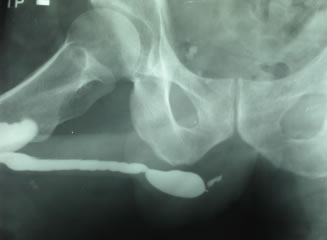

Восходящая уретрография – дефект

наполнения артефициальной уретры в области пеноскротального

угла, остановка контрастов в бульбозной уретре.